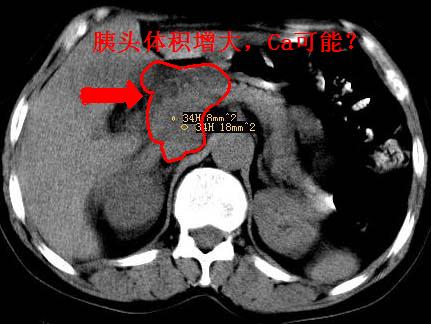

以下是引用卜一在2007-10-17 19:12:00的发言:[br]无增强,很难说!高度可疑:胰头癌?胆囊病变?肝左叶占位?

以下是引用王维浦在2007-10-17 21:02:00的发言:[br]胆囊增大,囊壁明显不规则增厚,邻近肝组织浸润,肝内外胆管无扩张。诊断:胆囊ca;[br]胰头软组织肿块影,考虑是由转移肿大的胰后淋巴结、没有肠道准备的十二指肠及胰头共同形成。[br]

以下是引用zhangzexing在2007-10-18 7:13:00的发言:[br]支持胰头占位,慢性胆囊炎. 2.肝左叶前外侧段占位,血管瘤?建议增强

以下是引用刘振江在2007-10-17 19:42:00的发言:[br]没有增强,胰头癌?胆囊及肝左叶占位?